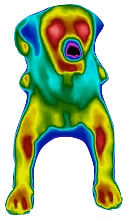

Bilder aus der Praxis:

Thermografie Hund liegend von vorn

Thermografie Hund liegend von vorn

Thermografie Hund liegend von vorn